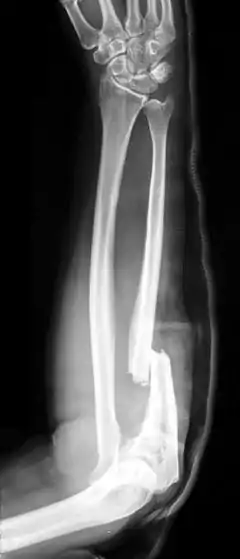

An isolated fracture of the ulna, also called a night stick fracture, is usually a sign of having defended oneself while protecting the head from being hit by a blunt object.[4][2] If associated with dislocation of radial head, it is called a Monteggia fracture, which can then be further classified according to the direction of displacement of the head of the radius at the elbow.[2]

Monteggia fracture

Side view of displaced fractured radius and ulna at wrist

Side view of bowing fractured radius and ulna